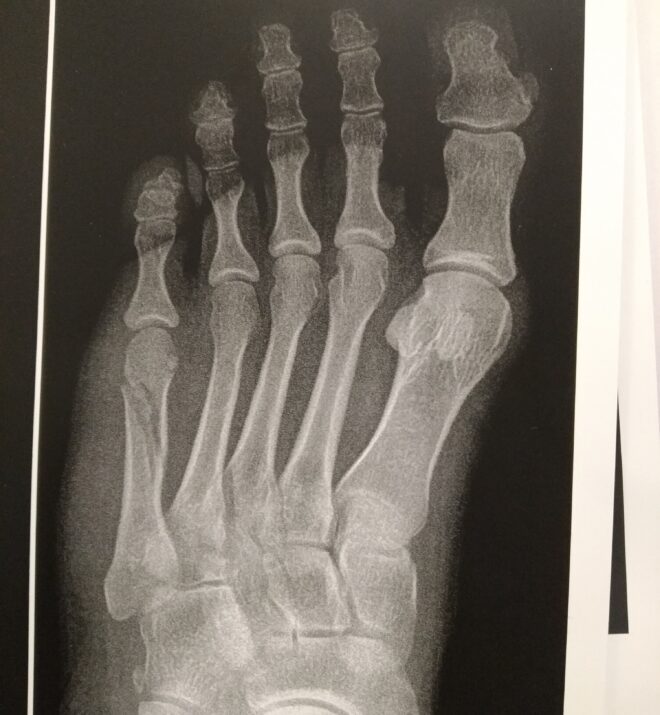

پرتوهای ایکس پا شکستگی مورب طولی شفت متاتارس پنج (شکل ۲ را ببینید) را نشان می دهند. اندازه قطعه شکستگی ممکن است بسیار متفاوت باشد.